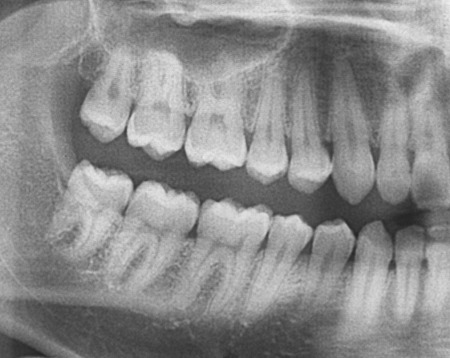

親知らずは生え方によってどうするべきか色々な場合があります。

(1) まっすぐ完全に生えて、咬み合っている場合

⇒まったく抜歯の必要なし

(2) まっずく生えているけど、半分埋まっている場合

⇒もう少し待てば、生えてきたり歯茎が縮まって見えてくるかもしれません。特に腫れた事が無ければ、このまま良く磨いて様子を見ましょう。

(3) 斜めに生えていて、半分埋まっている場合

⇒斜めに生えていると食片が詰まったままになり易く腫れる可能性があります。特に腫れた事が無ければ、このまま良く磨いて様子を見て腫れてから抜くか、先に抜いても良いと思います。

(4) 真横を向いていて、少し頭が見えている場合

⇒この時も(3)と同じで、様子を見ても良いし、抜いても良いと思います。

(5) 完全に埋まっている場合

⇒特に腫れた事が無ければ、そのまま様子を見て何か問題が有ればその時に抜くで良いと思います。